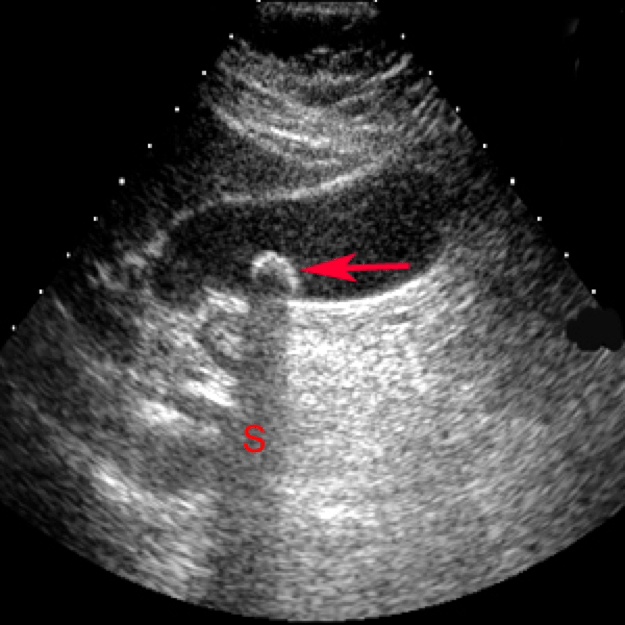

Полип Желчного Узи Фото

Полип Желчного Узи Фото 110 фотографий